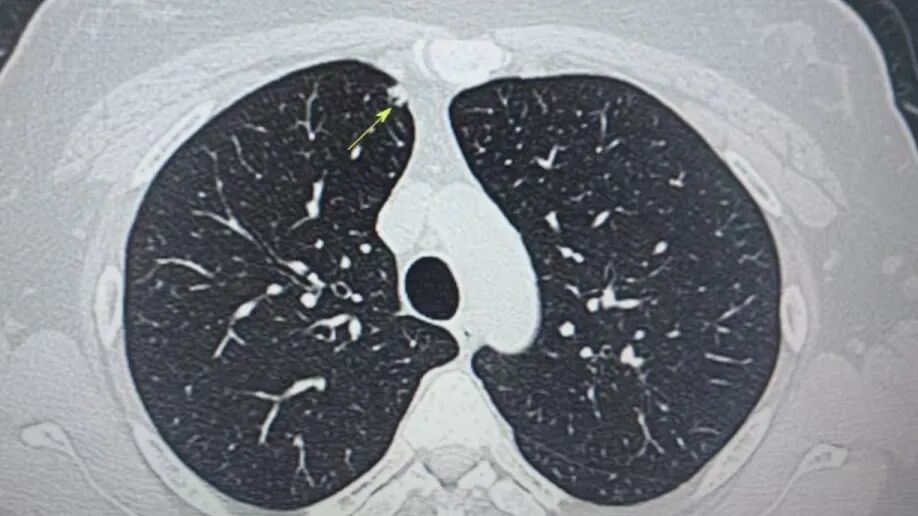

內(nèi)容提要 近年來,肺結(jié)節(jié)檢出率持續(xù)攀升,其發(fā)病群體正呈現(xiàn)明顯年輕化趨勢,更令人警醒的是,有些結(jié)節(jié)雖小,卻暗藏致命風(fēng)險(xiǎn)。葫蘆島市第二人民醫(yī)院肺結(jié)節(jié)診治中心近期接診的35歲劉女士(化名)便是典型一例:她體內(nèi)兩顆直徑僅4mm和6mm的“迷你”結(jié)節(jié),竟被病理證實(shí)為惡性腫瘤!這一案例再次顛覆了公眾對“結(jié)節(jié)小=安全”的固有認(rèn)知。 專業(yè)研判 為生命贏得轉(zhuǎn)機(jī) 微創(chuàng)精準(zhǔn)切除 四級手術(shù)顯實(shí)力 小結(jié)節(jié)≠低風(fēng)險(xiǎn) 認(rèn)知誤區(qū)亟需破除 人民醫(yī)院 人民名醫(yī)